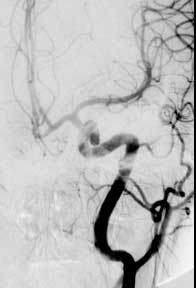

Findings: RCC angio shows the ICA follows an aberrent course, dipping inferiorly then laterally with no right A1 segment. A lobulated aneurysm involves the right MCA bifurcation. A second smaller aneurysm is present at the origin of the anterior temporal branch off the distal M1 segment. The normal left CC angiogram is shown for comparison.